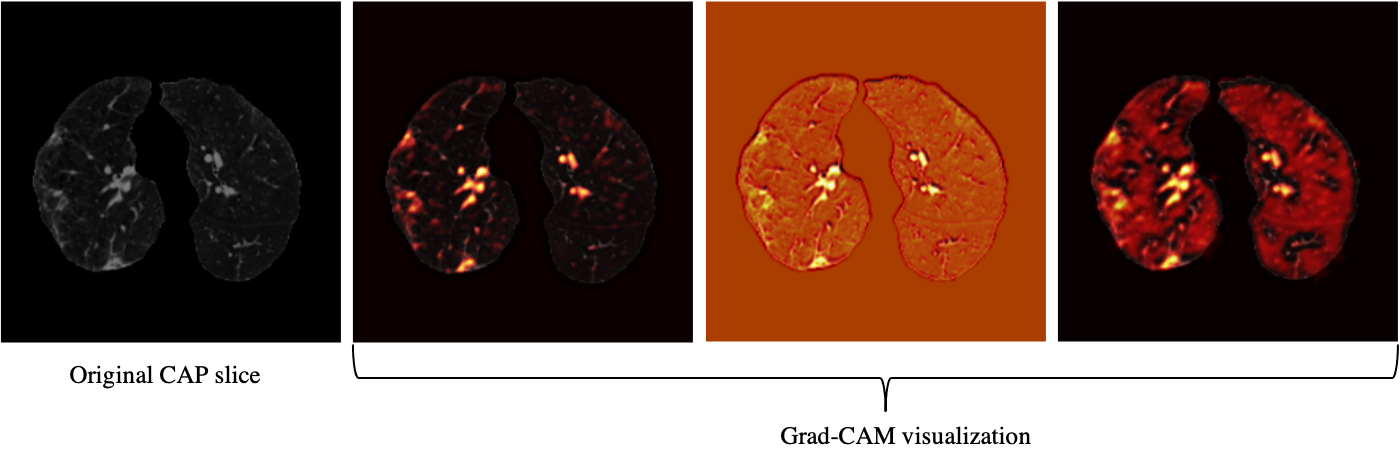

Refer to caption

Figure 4: Grad-CAM visualization of one CAP slice. This figure shows that the proposed AI model is paying attention to relevant locations of the image.

Based on the CT scans only, we analyzed the misclassified COVID-19 cases through all folds (11 cases in total), and studied their relation with the disease severity, coming to the conclusion that 4 out of 11 cases, did not have any related imaging findings, 5 were scored 1 by the three radiologists, one was scored 2, and only one case was scored at 3, which means the developed model is less likely to misclassify severe cases. Neither the developed model nor the experienced radiologist was able to detect the 4 COVID-19 cases without imaging findings, using CT scans only. Furthermore, since the CAP patients come from a different cohort and scanned with a standard dose, we visualized the model’s output for CAP cases, one of which is shown in Fig. 4, using Grad-CAM localization technique. This figure shows that the model is paying more attention to disease-related regions of the image, rather than dose-related ones. We performed the same localization technique on two slices with infection of the same COVID-19 patient, shown in Fig. 5.

Grad-CAM Visualization

We utilized the Grad-CAM localization mapping method [36] to provide a deep insight into the intermediate layers and identify what components in a CT image have obtained the most attention by the model. The Grad-CAM method extracts the spatial information, which is preserved by the convolutional layers and specifies the parts in the image having the most contribution to the final prediction. More specifically, the Grad-CAM method generates a localization heatmap corresponding to each layer and the target class to determine the locations to which the model paid the most attention. This localization heatmap is derived by a weighted average of all feature maps in the convolutional layer followed by a Rectified Linear Unit (ReLU) activation function.

Our study has some other limitations. First, the dataset is collected from a single centre, and experiments are required to verify its performance on data from external institutes, as it is critical to investigate if the model generalizes to diverse population [28, 29]. Vulnerability to data shifts, and bias against underrepresented population [28] are also crucial to address before the AI model can be put into practice. It is worth mentioning that as the extra set of 100 positive COVID-19 patients are collected in a disjoint time interval from the original set, it can act as a narrow validation [29]. It is, however, collected from the same institute and thus does not account for broad validation. It is also of high interest to explore domain validation for COVID-19 diagnosis, where test set comes from different variants. Second, the sample size is relatively small. Verifying the model’s performance on larger multi-centre datasets is the goal of our upcoming studies. The capsule network used in our study, is capable of handling small datasets compared to conventional models and due to fewer trainable parameters it is less prone to over-fitting, however, larger datasets can still improve the performance of the model. We also aim at expanding the proposed AI model to predict the disease severity besides the diagnosis. Moreover, although as shown in Figs. 4 and 5 visualization of the AI model’s output shows it is paying attention to relevant regions, more research is required to increase its explainability. Low performance on COVID-19 cases without imaging finding is another limitation of the developed model.